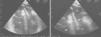

On return to the CCU, the patient experienced complete relief of chest pain and ST-segment normalization on the ECG. Nonetheless, her oxygen saturation level was still 90% despite high-flow oxygen by mask. A full transthoracic echocardiogram examination was then performed. A mass consistent with a thrombus was noted in the left atrium, appearing to arise from a redundant interatrial septum, while the right ventricle was moderately dilated with positive McConnell sign and the interventricular septum was displaced into the left ventricle, which was D-shaped in short-axis view (Figure 3). The pulmonary artery was dilated and the flow across the pulmonary valve suggested severe pulmonary hypertension with pulmonary artery systolic pressure estimated at 70 mmHg. In apical 4-chamber view, color flow imaging of the interatrial septum showed a right-to-left shunt. It was then decided to perform transesophageal echocardiography (TEE) to better characterize the relationship of the mass with the interatrial septum and its embolic potential, and also to look for masses in the right atrium. TTE showed a long thrombus that appeared to be attached to the atrial septum in the region of the foramen ovale. Color flow imaging was consistent with a patent foramen ovale (PFO) and the atrial septum was aneurysmatic. The thrombus had a snake-like movement inside the left atrium and its distal end was freely mobile, prolapsing through the mitral valve (Figure 4). No mass was observed in the right atrium or pulmonary arteries. Thoracic computed tomography angiography revealed bilateral thrombi in the main and lobar branches of the pulmonary artery (Figure 5).